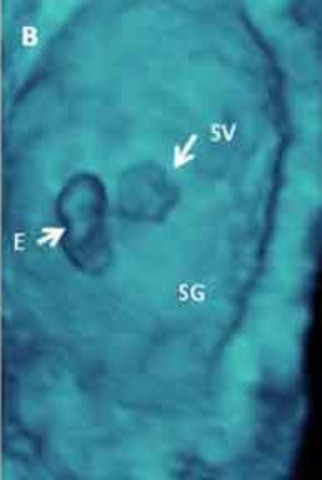

Lo gametos derivan de las celulas germinales primordiles (CGP) que se forman en el epiblasto .

Las celulas germinales primordiales que se formaron en el epiblasto, se transladan a la pared del saco vitelino. En lo fisico de la madre se nota un aumento en el tamaño de los pechos, cansancio, irritabilidad, alguna sensación de nausea.